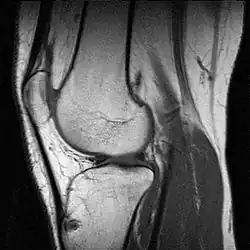

Magnetická rezonance (též MR, MRI, z anglického „magnetic resonance imaging“) je zobrazovací technika používaná především ve zdravotnictví k zobrazení vnitřních orgánů lidského těla. Pomocí MRI je možné získat řezy určité oblasti těla, ty dále zpracovávat a spojovat až třeba k výslednému 3D obrazu požadovaného orgánu. Magnetická rezonance využívá silné statické magnetické pole (řádově jednotky T) a elektromagnetické vlnění (s frekvencemi v řádu desítek až stovek MHz). Na rozdíl od CT vyšetření, které je s MR někdy alternativní, nenese žádná rizika způsobená ionizačním zářením (nulová radiační zátěž). Nevýhodou vyšetření MR je určitá hlučnost zařízení. Podstatou odlišení jednotlivých tkání a patologií je jejich rozdílné chování při stejném vnějším působení. Vyšetření se provádí bez kontrastní látky nebo s ní (např. gadolinium vpichem do žíly).

Výhodou MRI vůči ostatním zobrazovacím metodám v diagnostické radiologii je větší přesnost při zobrazení většiny orgánů, jež je důsledkem rozdílné intenzity signálu u odlišných měkkých tkání. Navíc toto zobrazení probíhá bez možného škodlivého ionizujícího záření. Některé orgány jako nervy či mozková tkáň bylo možné neinvazivně zobrazovat až právě pomocí MRI. Díky rozsahu nastavení vyšetření je možné dosáhnout rozlišení, které dalece přesahuje možnosti rentgenu či CT. Dalšího zlepšení může být ještě dosaženo podáním kontrastní látky, která pomůže odhalit přítomnost zánětů nebo nádorových tkání.